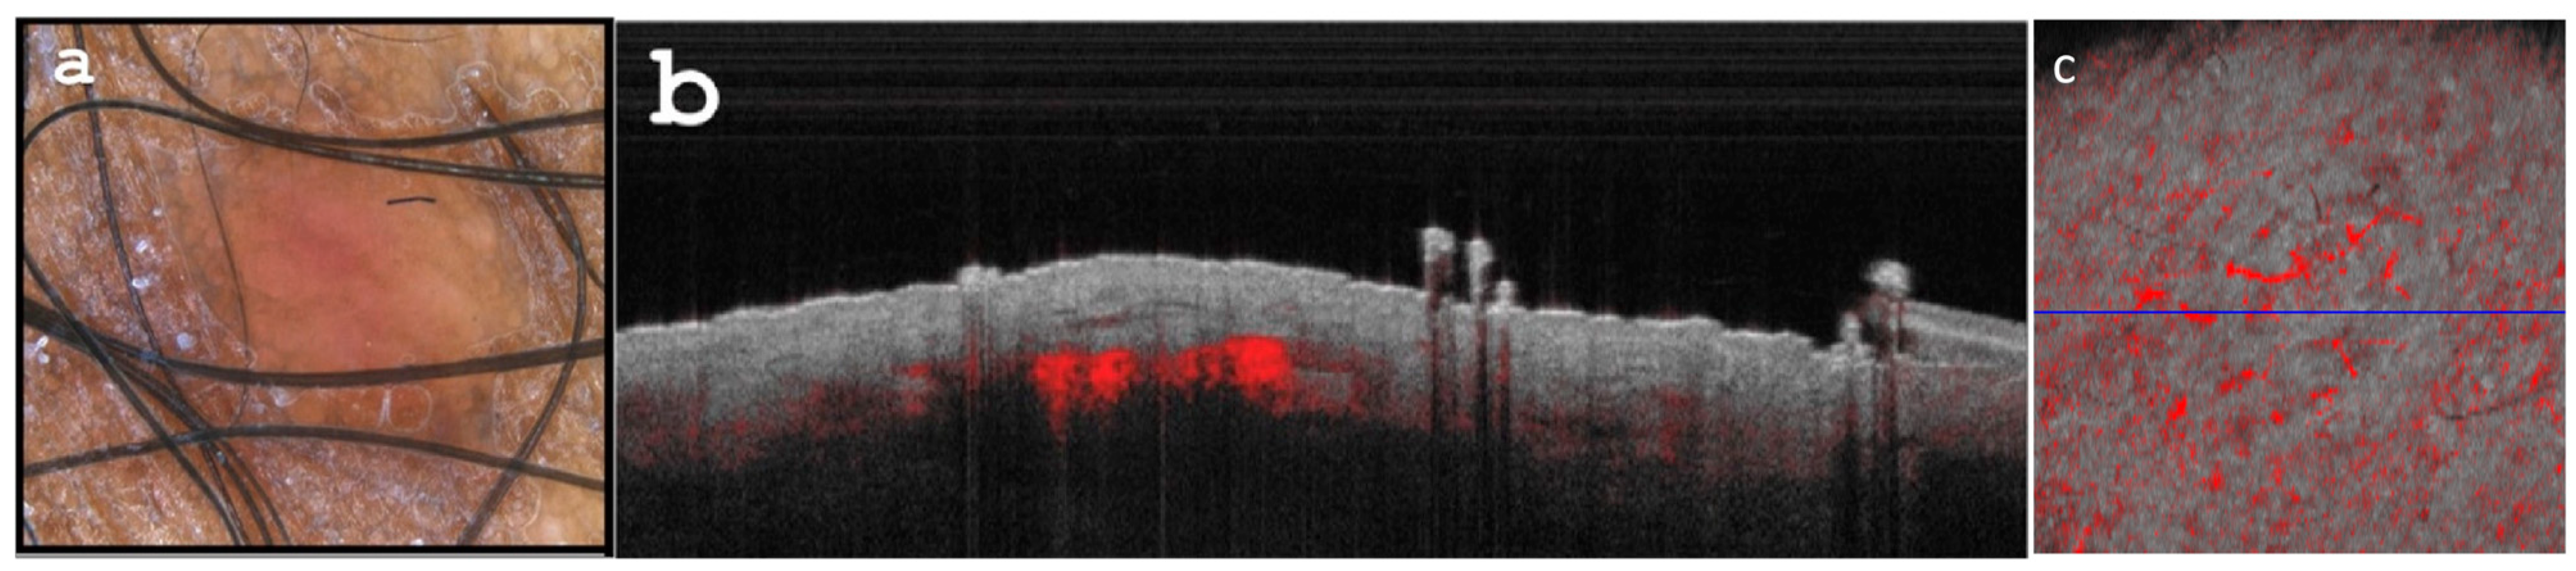

Dermoscopy revealed faint nodular structures on a red whitish background (Figure 2a). OCT was utilized to evaluate the lesions (Figure 2b–d). Lesional vascularization was assessed by measuring diameter and analyzing branching patterns, following established OCT standards.

Figure 2. (a) Dermoscopy depicts a blue-violaceous papular lesion exhibiting peripheral fading and a white-shiny glare, consistent with anisotrichosis. (b) Optical Coherence Tomography (OCT) cross-sectional capture reveals a nodular area with dermal attenuation, accompanied by visibly enlarged lesional vascularization (indicated by yellow stars). (c) Tissue inhomogeneity visible on OCT (yellow circle). (d) Enface OCT image: Demonstrating enhanced, branching vascular pattern (64 qm diameter) at a depth of 0.3 mm.

Figure 3. (a) Dermoscopy reveals the flattening of the lesion with persistent, yet reduced inflammation. (b) Optical coherence tomography (OCT) B scan (cross-sectional capture) displays diminished dermal attenuation and a scarce, thinned vascular pattern. (c) Enface OCT image showcases diminished vascularization (with a diameter of 40 qm) obtained at a depth of 0.3 mm, following topical imiquimod treatment.